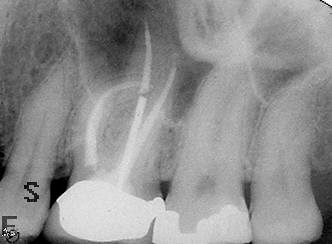

Excellent diagnosis essentially begins with two fundamental components: a doctor willing to listen to the patient’s chief complaint, and proper diagnostic tools. Among the most important tools are a precise periapical radiograph (PA) and bitewing (BW). Although a PA is often enough to provide an accurate portrayal of the patient’s condition, sometimes it alone does not suffice. Figure 1, Figure 2, and Figure 3 demonstrate a case that illustrates this point clearly. Despite two acceptable PAs (Figure 1 and Figure 2), it is difficult to assess the source of the patient’s pain to temperature. However, the BW radiograph Figure 3 provides significantly more clarity than either of the two PAs. The BW depicts localized bone loss (around tooth No. 2), a pulp stone (No. 2), a flat occlusion, numerous calcified canals, multiple restorations in tooth No. 30, and gross decay especially on tooth No. 3, which is the source of the patient’s pain to temperature. In this instance these images depict how much more useful a BW can be than just a conventional PA.